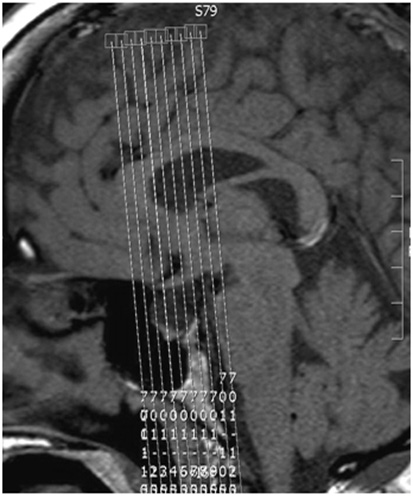

| SAG | T1 | 3D TSE | 0.7-1.0 | 0 | no | 18 | AXIAL, COR | Center on pituitary. L-R coverage 8 cm. Angle to interhemispheric fissure. |